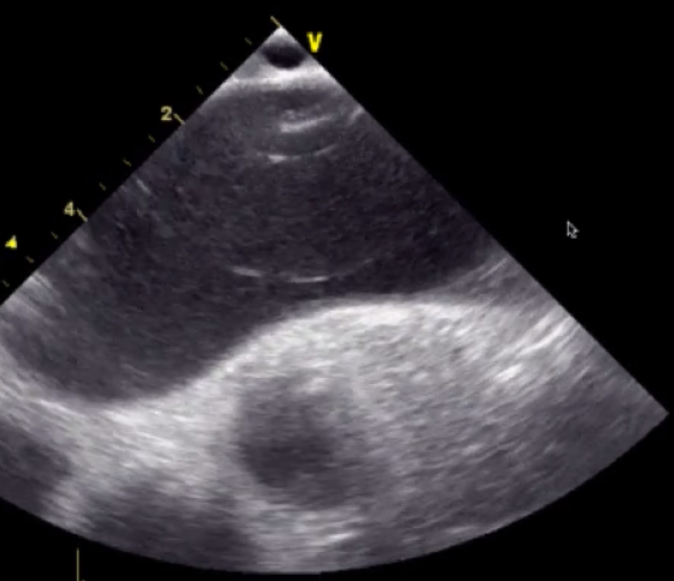

Label 1

RV

Label 2

Pulmonic Valve

Label 3

Right Coronary Cusp

Label 4

Left Coronary Cusp

Label 5

Non-Coronary Cusp

Label 6

Main Pulmonary Artery

Label 7

Left Pulmonary Artery

Label 8

Right Pulmonary Artery

Label 9

Left Atrium

Label 10

Right Atrium